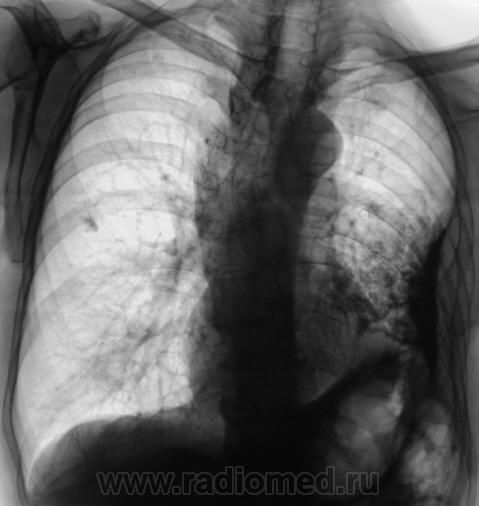

• https://radiomed.ru/sites/default/files/styles/case_slider_image/public/user/12/103.Dela__0.jpg?itok=lf15evZc

Томограммы.

Какие мнения?